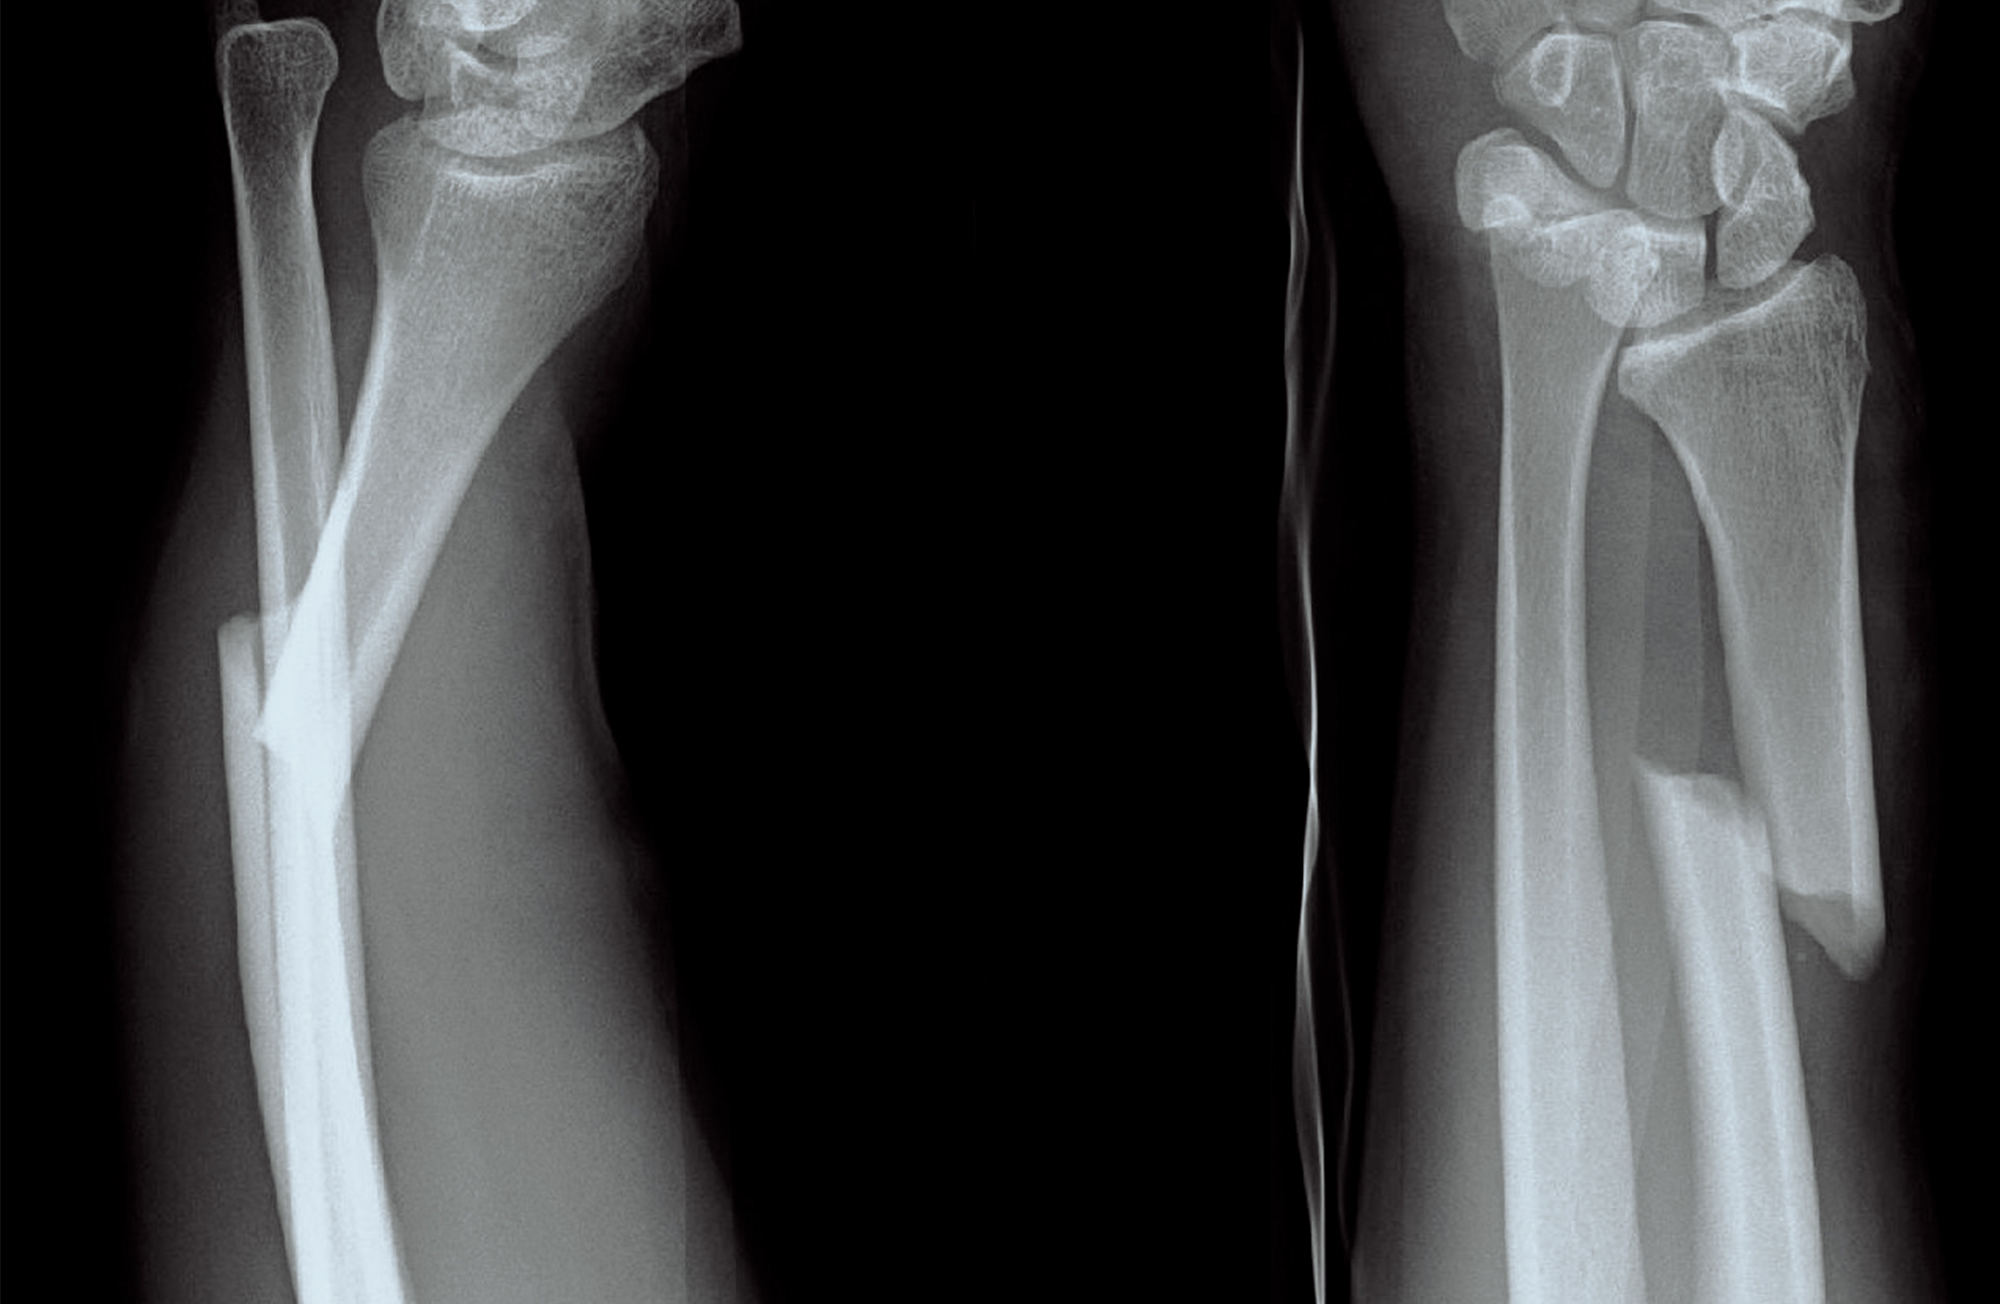

Galeazzi-Fraktur (Galeazzi fracture) / Th. Zimmermann / CC SA 3.0 Germany. Image has been cropped.

Eighteen months ago, I sustained a serious arm and wrist fracture falling down our staircase. It is called a Galeazzi fracture, a very sophisticated name for a tremendously awful injury. Less than seven percent of people are diagnosed with this kind of fracture. My husband joked that I have always been an overachiever. After emergency surgery, new hardware, and a pinned wrist, I thought the worst was over. Was I ever wrong.